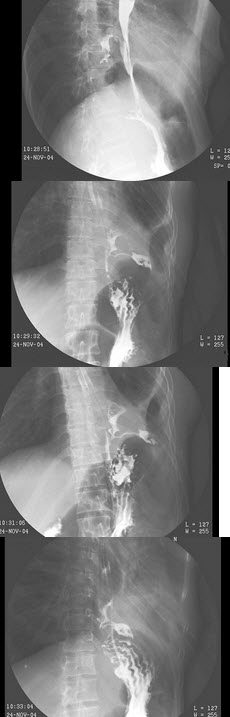

E.肺门处出现了残根状表现

男,61岁,进行性吞咽困难40天,体重减轻5kg,结合图像,最可能的诊断为()

A.外压改变